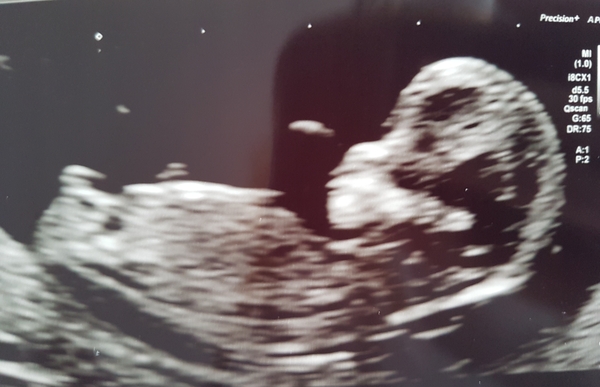

KLane · 04/03/2019 11:03

Parent19876 · 04/03/2019 11:04

Hey ladies!

Twelve week scan went very well today- little frog wouldn't wake up and was laying on their side, so was sent off to drink more and have a walk around. Ate some sweets and seemed to do the trick!

New due date is 9 September, so now 13 weeks!

Can't wait to hear how everyone else's scan went!

hodgeheg92 · 04/03/2019 12:24

Congrats @megan2018 and @parent19876, lovely scan photos even if babies were a bit tricky!